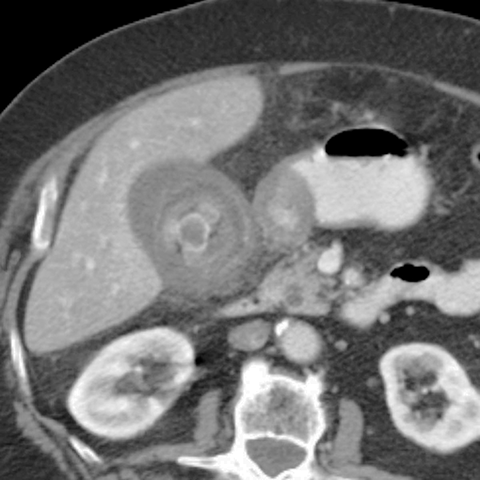

Cholelithiasis, CT